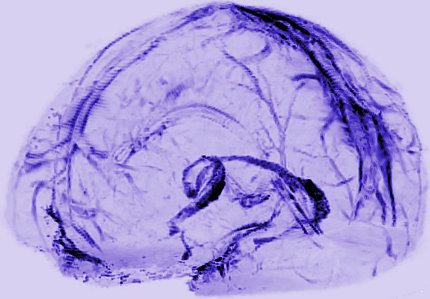

Image of brain vessels

Scientists saw evidence that brains may drain waste via lymphatic vessels.